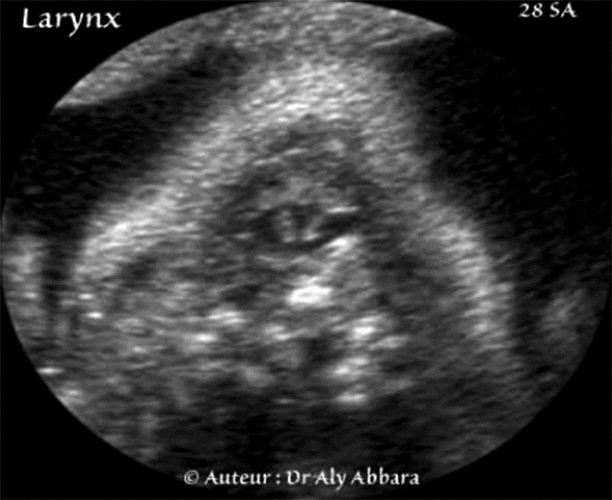

Lrynx foetal à 28 SA -Anatomie échographique

Coupes axiales cervicales centrées sur le larynx

(Fœtus âgé de 28 SA).

• Coupes échographiques axiales cervicales centrées sur la partie supérieure de la voie respiratoire ; elles permettent la mise en évidence du larynx sur trois niveaux de hauteur (du haut vers le bas) : on remarque aussi :

• toujours l'épiglotte surmontant le larynx en avant ;

• l'ouverture du larynx (ou la glotte) limitée bilatéralement par les deux cordes vocales droite et gauche.